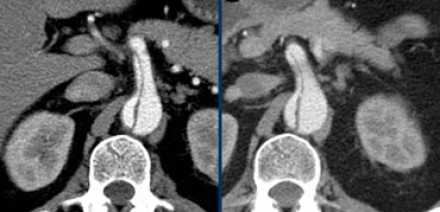

![11]()

- Слева представлен пациент со Stanford A. Диссекция с четкой визуализируемой интимой.

- Справа представлен пациент со Stanford B. Патология локализована в нисходящей аорте. «Точка входа» расположена ниже уровня левой подключичной артерии.

Радиологические находки

- На ниже лежащих снимках представлен пациент с диссекцией типом B. Истинный просвет окружен кальцификацией. Истинный просвет узкий и подвергается компрессионным изменениям, обусловленных систолическим давлением.

- При диссекции аорты интима визуализируется по старым данным только в 70% случаев, но связи с развитием техники данный показатель на сегодняшний день составляет выше 90%.

- На ниже представленных изображениях представлена диссекция типа B.

- Истинный просвет, окружен кальцификатами.

- Истинный просвет уже, чем ложный просвет, а также четко визуализируется симптом клюва.

- В ложном просвете локализован тромб, который контрастируется позже истинного просвета.